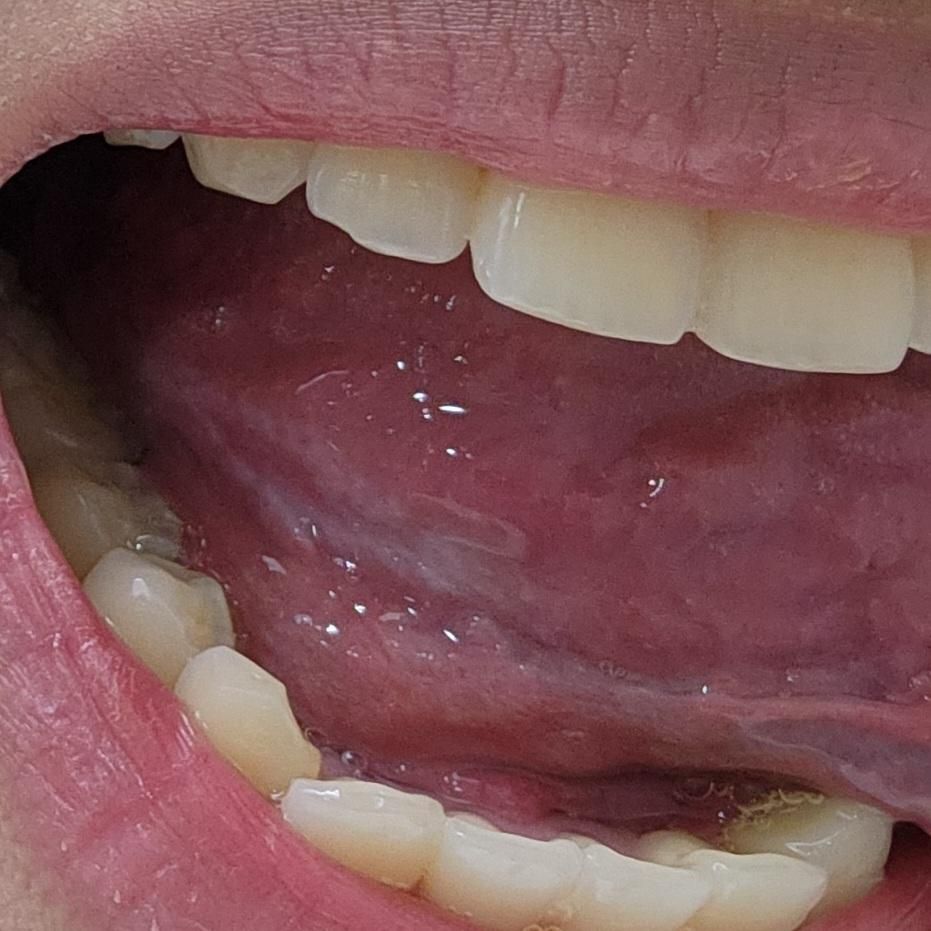

혀 아래쪽 부분을 지속적으로 깨물어가지구 이렇게 됐어용...

사진에 보이듯이 안쪽은 빯갛고 겉은 하얀색입니다...혹시 괜찮은걸까요??? 너무 걱정되용....ㅠㅠㅠㅠㅠㅠㅠㅠㅠㅠ 느낌상 거의 한달전부터 자주 깨물어서 아래쪽이 아팠는데 최근에 보니깐 이렇게 보이네용...ㅠㅠ

혀 아래쪽을 지속적으로 깨무는 습관으로 인해 생긴 빨갛고 겉은 하얀 병변은 만성적인 물리적 자극에 의한 자극성 궤양 또는 백반증(Leukoplakia) 가능성이 있습니다. 단순한 염증이나 궤양은 며칠 내 자연적으로 호전되지만, 1개월 이상 지속되거나 하얀색 각질층처럼 보이는 병변이 있을 경우는 정밀한 확인이 필요합니다.

특히 반복적 자극 부위는 드물게 전암성 (암 전단계) 병변으로 발전할 수도 있어 과거력과 증상 지속 기간이 중요해요

따라서 이 경우에는 단순히 괜찮다고 넘기기보다는 구강외과 또는 이비인후과에서 진료 후 조직검사 여부를 판단받는 것이 안전합니다. 현재처럼 반복적으로 깨무는 원인을 찾는 것도 중요하며, 교합 문제턱관절 위치 이상, 스트레스성 습관 등이 원인이 될 수 있습니다. 자극을 줄이는 구강 보호기 착용이나 습관 개선도 필요할 수 있습니다